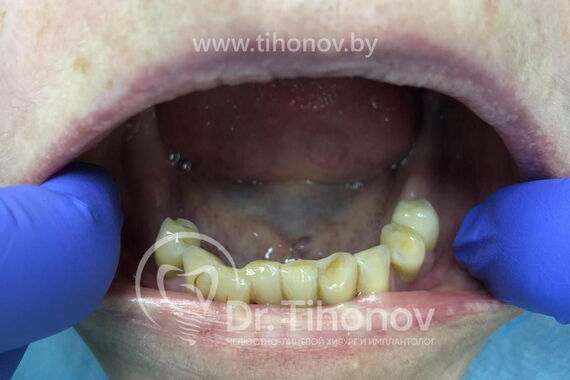

При изучении данных 3D-исследования, был выявлен недостаток высоты и толщины костной ткани на обеих челюстях. В связи с этим пациентке был предложен вариант быстрого и эффективного восстановления зубов на верхней и на нижней челюстях с использованием методики All-on-6 (все на 6-ти): были удалены оставшиеся зубы, установлены 6 имплантатов на верхней и 6 имплантатов на нижней челюстях, в течение 5 дней изготовлены и зафиксированы в полости рта несъемные эстетичные и функциональные протезы на обе челюсти. Таким образом, пациентка обзавелась красивой улыбкой за 5 дней.